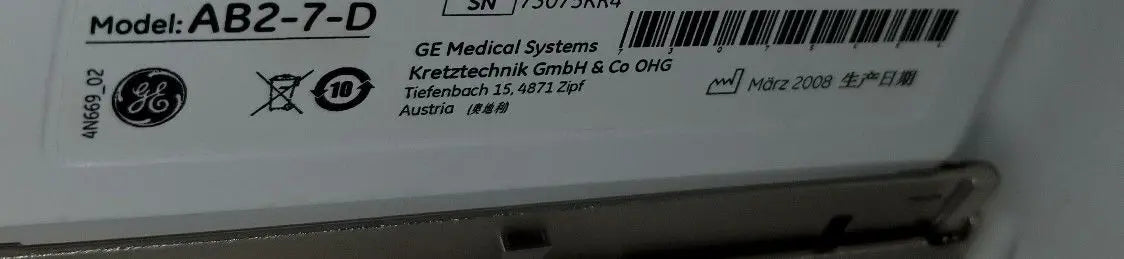

Brand: GE

Model: AB2-7-D

Investing in the GE ultrasound probe means choosing durability and reliability. This transducer is built to withstand the rigors of a busy clinical environment, ensuring it remains functional over time. Regular calibration and maintenance are straightforward, which helps maintain its high performance. Additionally, the probe is compatible with a range of GE ultrasound systems, making it a versatile choice for many medical facilities. Therefore, healthcare providers can count on the AB2-7-D to deliver consistent performance day after day.